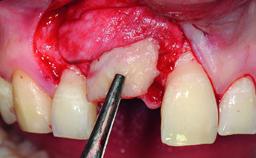

A 49-year-old female patient was referred for implant therapy to replace the upper right central incisor (tooth 11). The tooth had been assessed by an endodontist who diagnosed a vertical fracture of the root. The tooth had a hopeless prognosis and needed to be extracted. The patient was healthy and was not taking any medications. She was allergic to penicillin. The patient had high esthetic demands but her expectations were realistic. The extraoral examination revealed no facial asymmetries. The right temporomandibular joint demonstrated an opening click but was otherwise asymptomatic. The lip line was high with a significant gingival display.

Bone Augmentation Simultaneous|Vertical

Augmentation Materials Autogenous chips|Xenogenous|Membrane